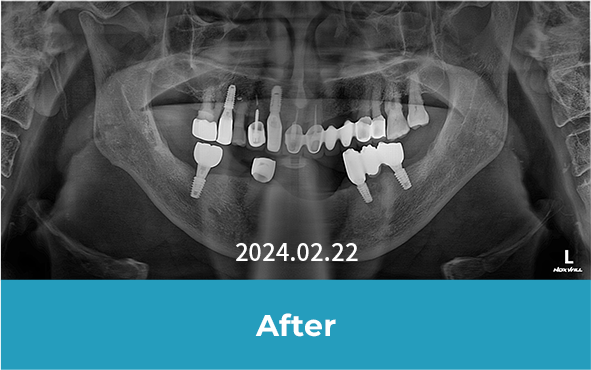

· 네비게이션 임플란트 / 임플란트 식립 2개월 후 보철물 체결 완료와 더불어 다량의 충치 크라운 치료 진행 case

• 치료 후 사진